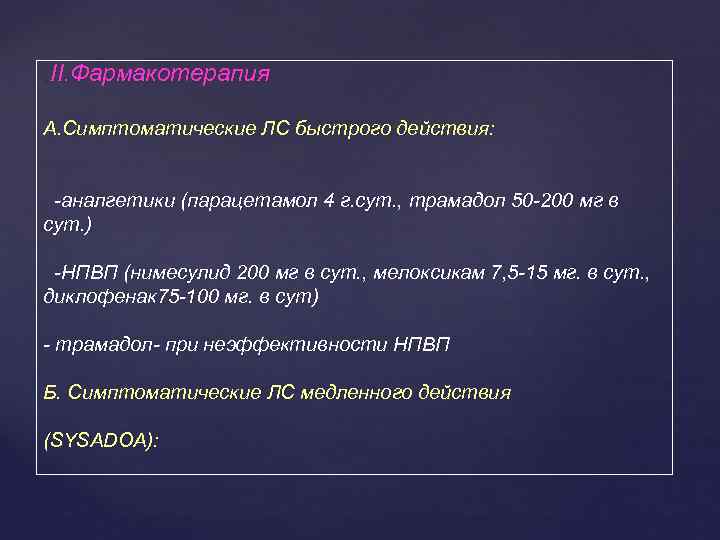

. II. Фармакотерапия А. Симптоматические ЛС быстрого действия: -аналгетики (парацетамол 4 г. сут. , трамадол 50 -200 мг в сут. ) -НПВП (нимесулид 200 мг в сут. , мелоксикам 7, 5 -15 мг. в сут. , диклофенак 75 -100 мг. в сут) - трамадол- при неэффективности НПВП Б. Симптоматические ЛС медленного действия (SYSADOA):

. II. Фармакотерапия А. Симптоматические ЛС быстрого действия: -аналгетики (парацетамол 4 г. сут. , трамадол 50 -200 мг в сут. ) -НПВП (нимесулид 200 мг в сут. , мелоксикам 7, 5 -15 мг. в сут. , диклофенак 75 -100 мг. в сут) - трамадол- при неэффективности НПВП Б. Симптоматические ЛС медленного действия (SYSADOA):